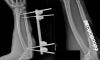

Годовалого мальчика из Воронежа, которого избила мама, выписали из больницы во вторник, 14 октября. Об этом корреспонденту TV Губернии рассказали в пресс-службе регионального минздрава. Малыш перенес несколько операций и провёл на больничной койке почти три недели. Ужасная история произошла в конце сентября в квартире одного из домов на Ленинском проспекте. 24-летняя девушка избила сына, видимо, из-за громкого плача. Малыш попал в больницу, где у него диагностировали серьёзную черепно-мозговую травму. Врачам пришлось удалить часть черепа. В отношении горе-матери возбудили уголовное дело по статье «Умышленное причинение тяжкого вреда здоровью малолетнего». 24-летней горожанке грозит до 10 лет лишения свободы. Сейчас девушка находится под стражей. В больнице с мальчиком находился его отец, который приехал, как только узнал о случившемся. Помощь мальчику оказывают в воронежском отделении Российского детского фонда. Пока малыш находился в больнице, ему передали одежду и гигиенические принадлежности. Сейчас же отцу пострадавшего помогают с юридическим сопровождением.